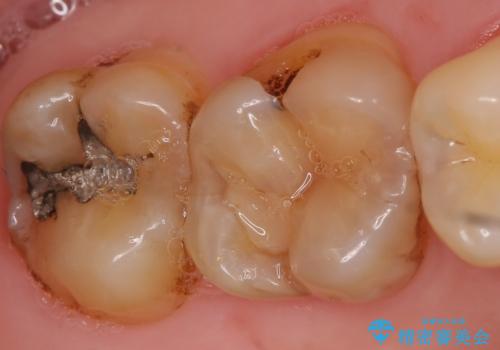

- 古い銀歯をセラミックで治療したいといらっしゃった方の症例です。

銀歯及び虫歯を除去後、セラミックインレーによる修復を行いました。